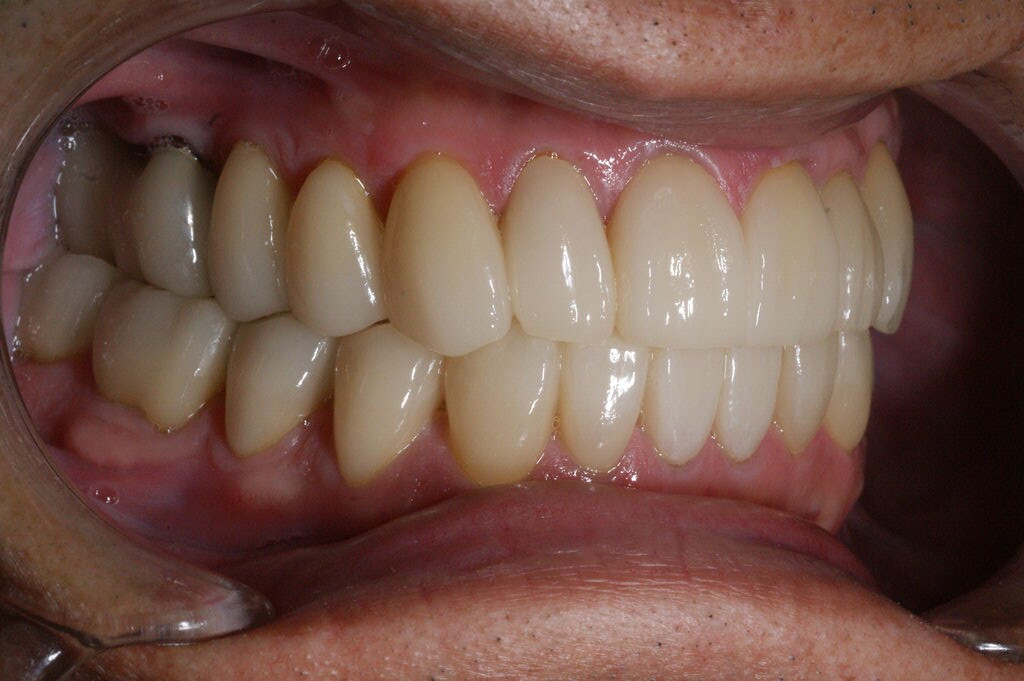

矯正治療終了後、模型を咬合器に付着し診断用ワクシングをしたところ、本来歯牙は咬合調整か小規模の修復処置で済めば極力そのまま使うのが理想ではあるが、長年の不正咬合とブラキシズムによる高度の磨耗のため、修復処置なしでは安定した咬合に基づく長期的な口腔内の健康は得られないとの判断に至る。

一口腔単位の長期的な健康維持のため、安定した咬合の確立と審美性の獲得を意図し全顎的修復処置を行う。(大)